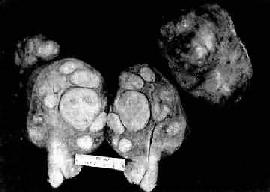

肉 眼观,肌瘤可以生长在子宫任何部位,常位于子宫壁内(肌层内肌瘤)、浆膜下(浆膜下肌瘤)或粘膜下(粘膜下肌瘤)。可单发或多发,常为多个,其数目多少不 等,常见为数个、乃至十数个或数十个,称多发性平滑肌瘤。肌瘤的大小可极为悬殊,小的在显微镜下才可检见,大的如成人拳大或更大,甚至可充满整个腹腔。肌 瘤多呈球形或融合成不规则形,质较硬,界限明显,但无明显包膜(图13-7)。切面上,瘤组织常呈灰白色,编织状或旋涡状,当肌瘤生长较快或供血不足时, 可发生各种继发性改变,如玻璃样变、粘液变、囊性变、水肿出血坏死等。

图13-7 子宫平滑肌瘤

多个肌瘤结节,位于肌壁内、粘膜下及浆膜下,境界分明,宫腔受挤压呈裂隙